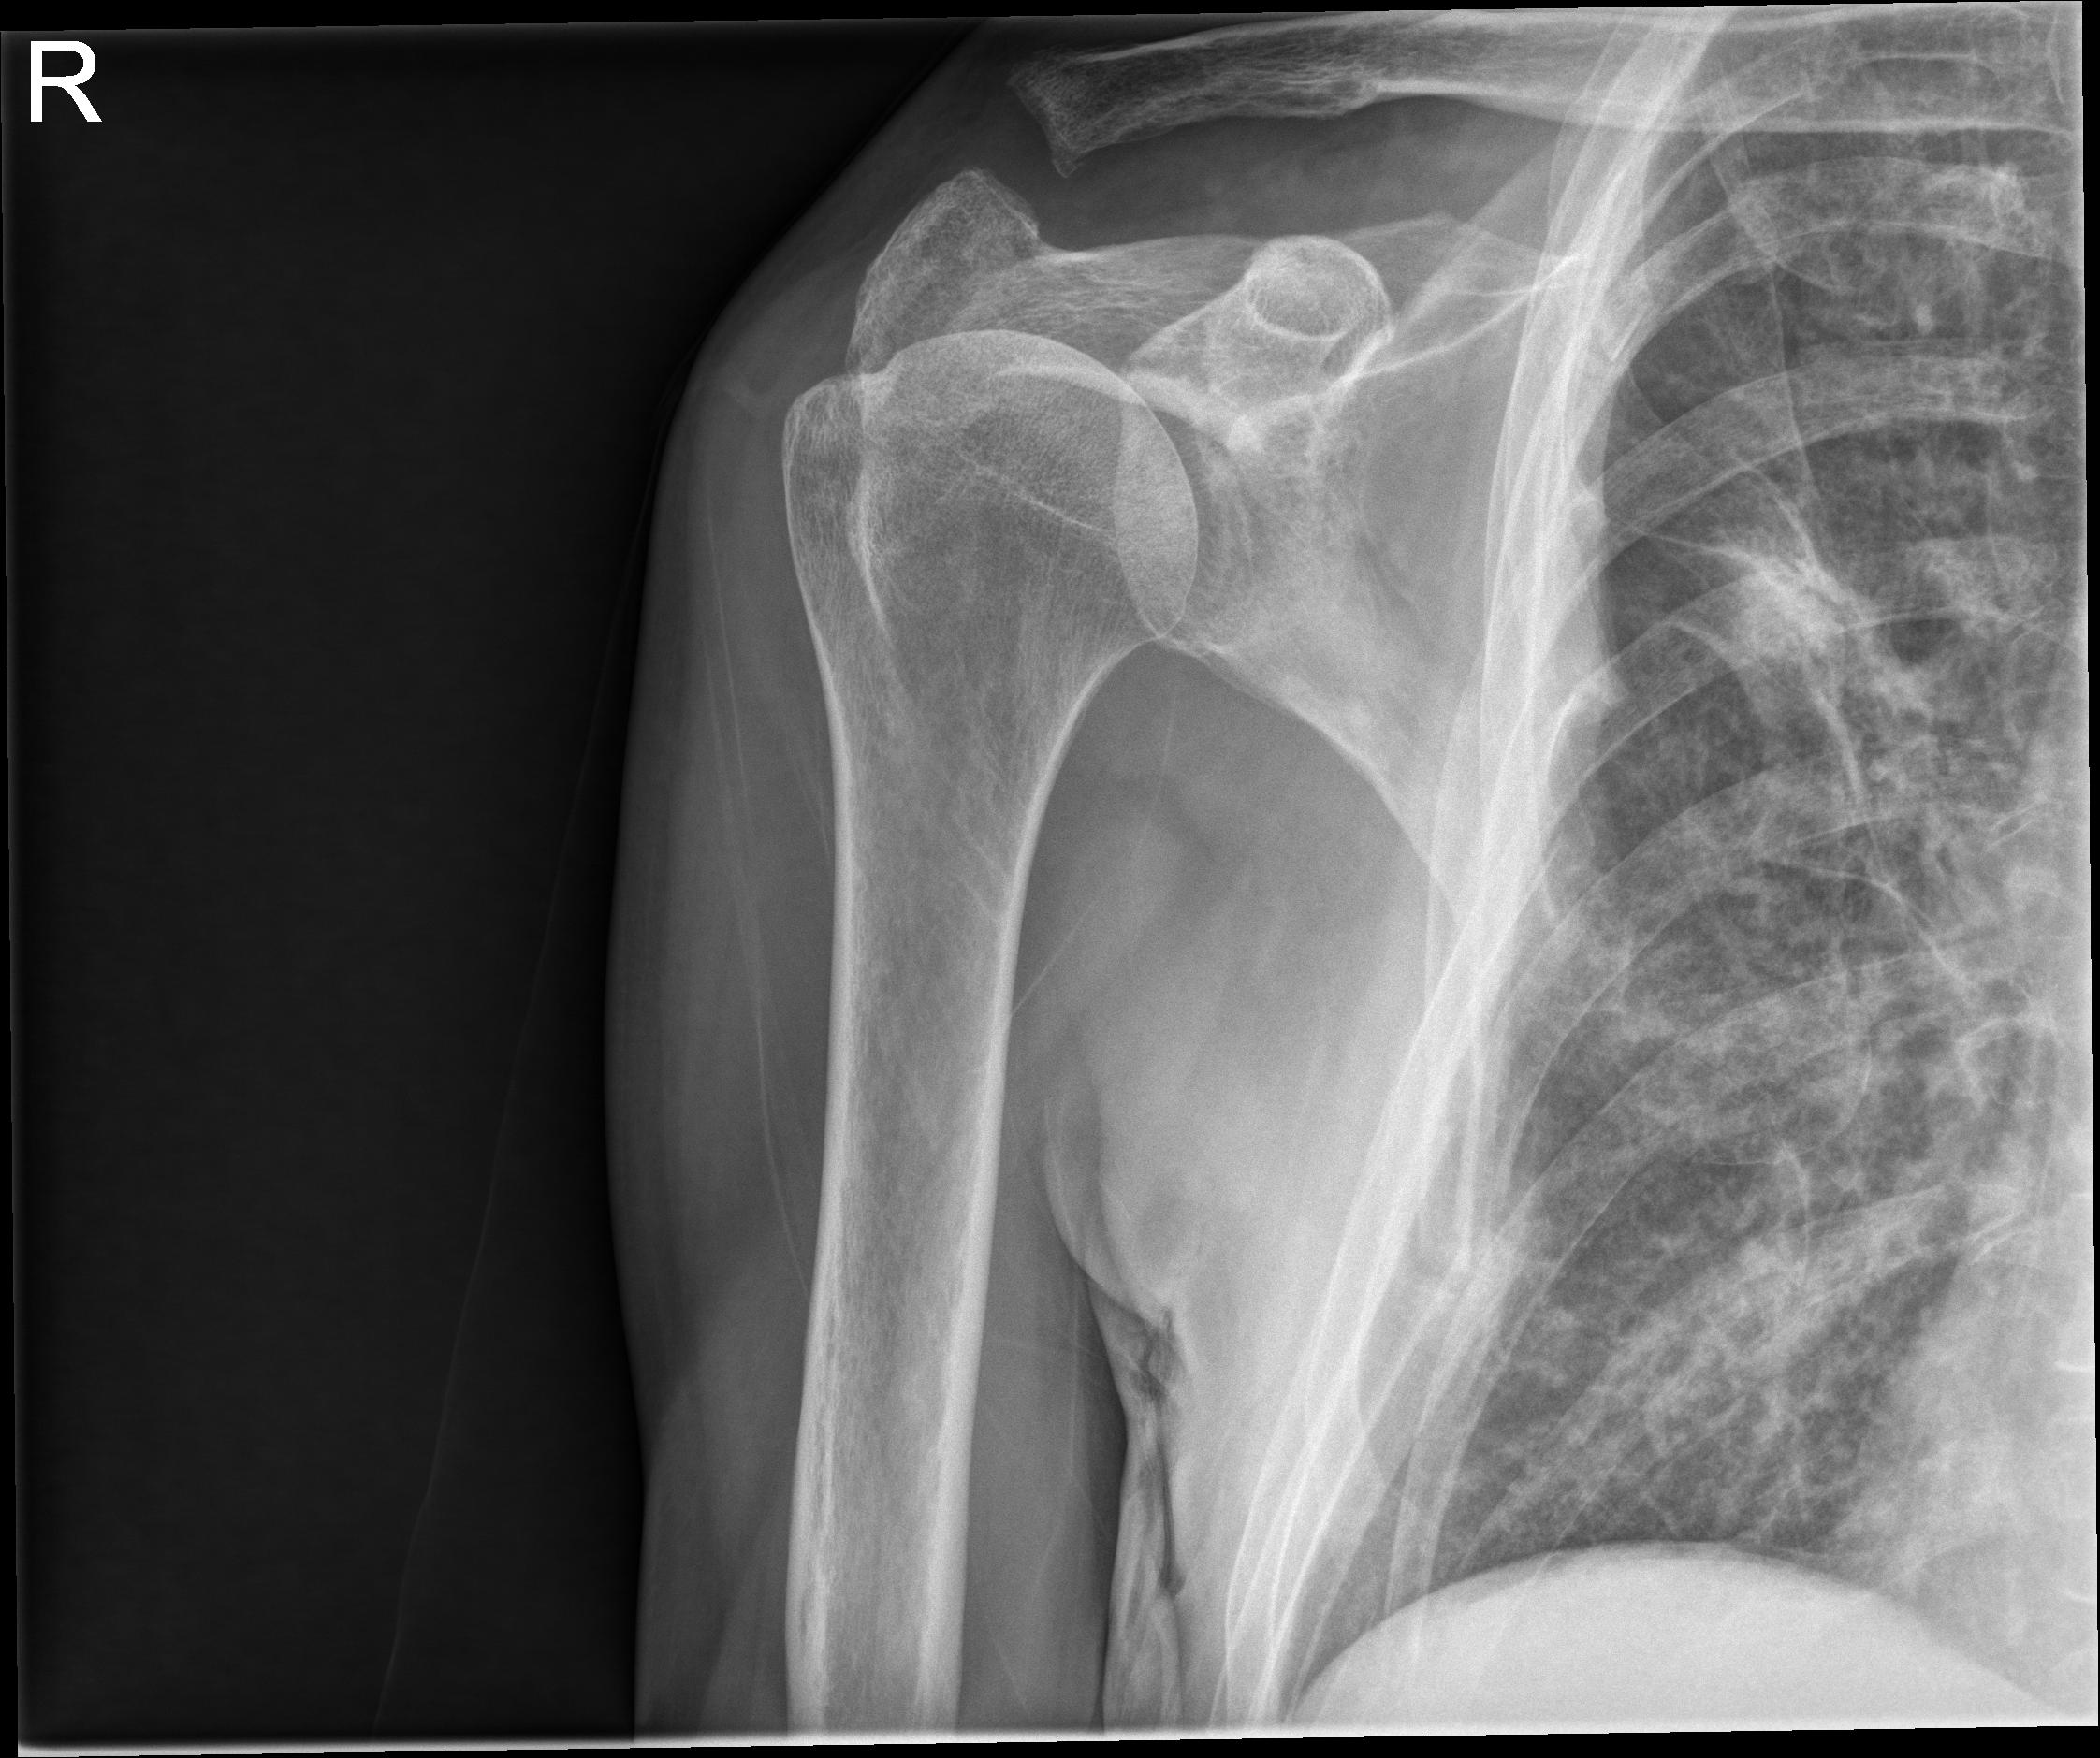

1 Hombro der.